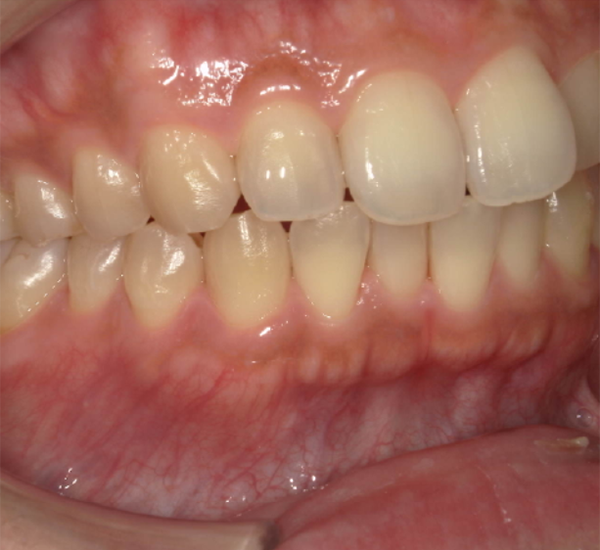

治療後

| 行った治療内容 |

こちらから歯みがき粉等はオススメしておらず、市販品でもよく行き届いていた方なので、以前に使っていた歯みがき粉と歯周病予防のものを使い分けるようにオススメしました。 一度着色除去をうけていただき、その後も着色もなく定期検診で拝見しています |

| 術後の経過・現在の様子 | もともと虫歯予防に励んでいた患者さんでしたので、艶があり綺麗な歯質をしていました。 通常の虫歯予防の歯磨き粉であれば清掃効果として研磨剤が入っていますので、お茶による着色は今までどおりご自身で落とせると思われます。 |

| 治療期間 | 1日 |

| 総額治療費の目安 | 着色除去5,000円+税 |